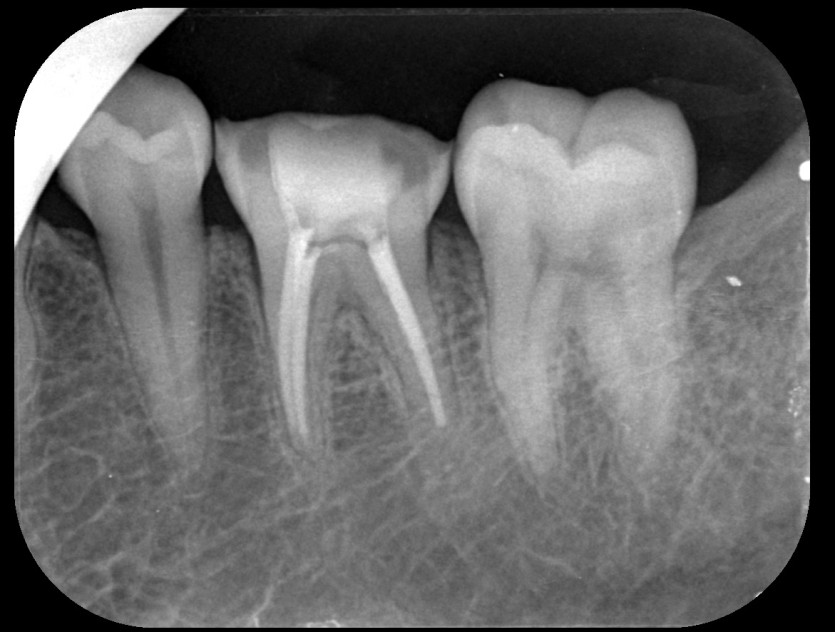

신경치료 사례